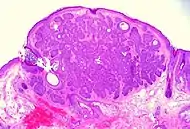

High-magnification micrograph of basal-cell carcinoma

Basal-cell carcinoma cells appear similar to epidermal basal cells, and are usually well differentiated.[25]

Nodular basal-cell carcinoma (also known as "classic basal-cell carcinoma") accounts for 50% of all BCC.[27] It most commonly occurs on the sun-exposed areas of the head and neck.[28]:748[29]:646 Histopathology shows aggregates of basaloid cells with well-defined borders, showing a peripheral palisading of cells and one or more typical clefts.[27] Such clefts are caused by shrinkage of mucin during tissue fixation and staining.[30] Central necrosis with eosinophilic, granular features may be also present, as well as mucin. The heavy aggregates of mucin determine a cystic structure. Calcification may be also present, especially in long-standing lesions.[27] Mitotic activity is usually not so evident, but a high mitotic rate may be present in more aggressive lesions.[27] Adenoidal BCC can be classified as a variant of NBCC, characterized by basaloid cells with a reticulated configuration extending into the dermis.[27]